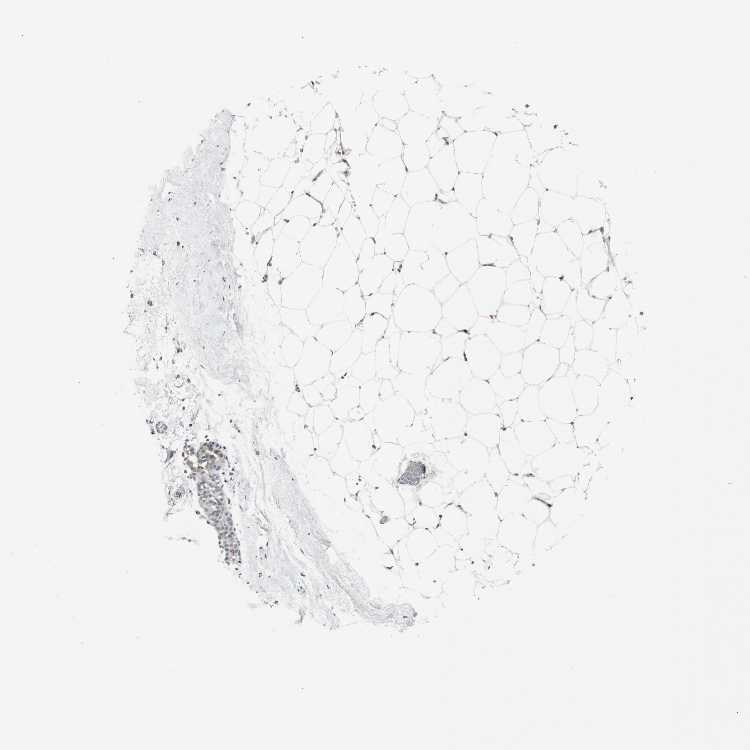

BREAST - Antibody stainingi

Antibody staining in the annotated cell types in the current human tissue is reported as not detected, low, medium, or high, based on conventional immunohistochemistry profiling in selected tissues. This score is based on the combination of the staining intensity and fraction of stained cells.

Each image is clickable and will lead to virtual microscopy that enables deeper exploration of all samples and also displays staining intensity scores, fraction scores and subcellular localization as well as patient and tissue information for each sample.

Antibody CAB005021Antibody CAB037248

Adipocytes Not detectedLow

Glandular cells Not detectedMedium

Myoepithelial cells Not detectedMedium